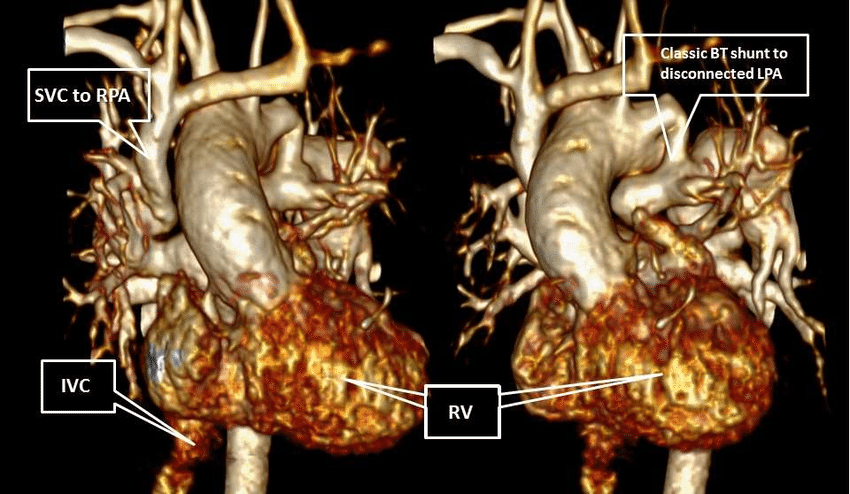

الرنين المغناطيسي على أنجيو الشرايين (MR Angiography)

يُعد الرنين المغناطيسي على أنجيو الشرايين من أحدث تقنيات تصوير الشرايين والأوعية الدموية، حيث يتيح تقييمًا دقيقًا للشرايين التاجية والأوعية الكبرى دون الحاجة إلى تدخل جراحي أو قسطرة.

يساعد هذا الفحص المتقدم في:

- تشخيص ضيق وانسداد الشرايين التاجية

- تقييم أمراض الأوعية الدموية المختلفة

- متابعة حالات تصلب الشرايين

- دعم التشخيص الدقيق ووضع الخطة العلاجية المناسبة

ويتميّز الرنين المغناطيسي على أنجيو الشرايين بأنه:

- عالي الدقة في إظهار تفاصيل الأوعية الدموية

- آمن في كثير من الحالات مقارنة بالفحوصات التداخلية

- مناسب للمتابعة طويلة المدى لبعض مرضى القلب والشرايين